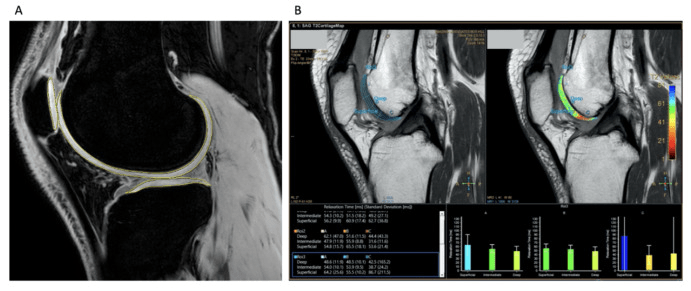

2024年7月26日,墨爾本干細胞研究中心牽頭在國際期刊《骨關節炎和軟骨開放》上發表了一篇關于《同種異體脂肪間充質干細胞制劑治療膝關節骨關節炎的安全性和有效性》的I/IIa期隨機對照試驗。[5]

這是一項單中心、雙盲、劑量遞增、隨機對照試驗。40名患有中度膝關節骨關節炎的患者隨機接受單次關節內注射MAG200(劑量組:10、20、50、100×106?細胞)或安慰劑。

- MAG200隊列報告的反應者比例高于安慰劑組,并且疼痛癥狀有臨床和統計學顯著改善,所有KOOS分量表均有臨床相關改善。(圖2)

- MAG200顯示出優于安慰劑的可重復治療效果,這對于10×106劑量組的疼痛具有臨床相關性,對于20×106和100×106劑量組的功能具有臨床相關性。

- 在MAG200 10、20和100 × 106劑量組中,觀察到疾病改善趨勢,膝關節軟骨總體積有所改善,而安慰劑組中骨關節炎有輕微改善。

- 治療耐受性良好,未發生與治療相關的嚴重不良事件。

綜上所述,在MAG200 10、20和100 ?× ?106劑量組中,觀察到疾病改善趨勢,膝關節軟骨總體積有所改善,而安慰劑組中骨關節炎進展不顯著。